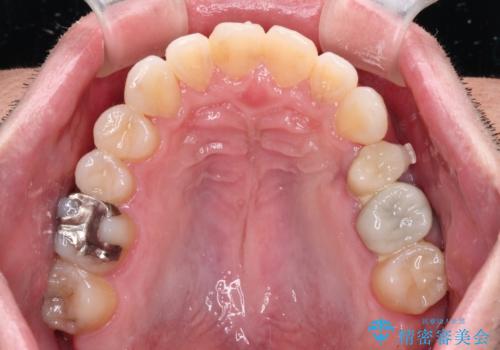

内側に転位した歯とボロボロのむし歯 インビザラインによる矯正治療とむし歯治療

矯正治療後には抜歯が必要な歯に隣接してむし歯となっていた歯をオールセラミッククラウンにて補綴治療を行うこととしました。

矯正治療開始時に、インビザライン矯正の加速装置を購入されましたが、インビザライン自体をあまりしっかりと使用できず、4年間の治療期間となりました。